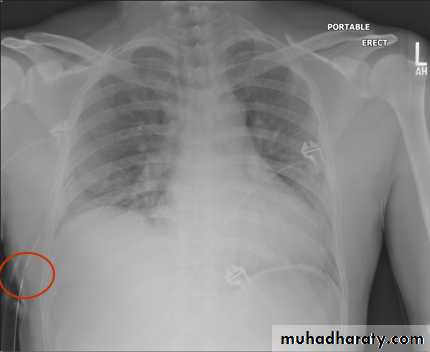

• Check up chest x-ray

Fall from the 2nd floor